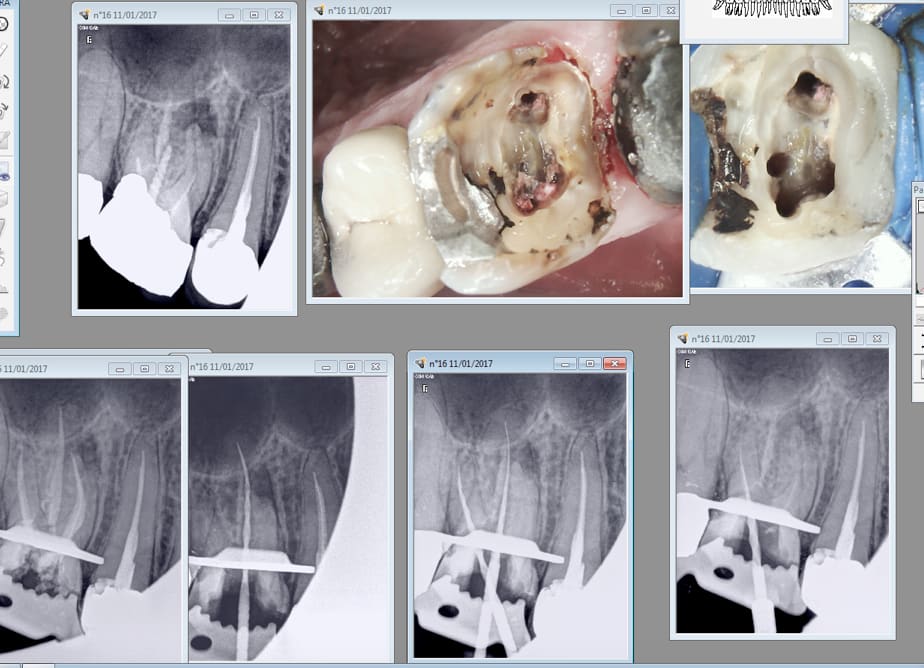

Bon si le réciproc blue résiste à un usage intensif. Ca n'est pas le cas des protapers gold.

Le dé-vrillage est plus difficile à détecter que sur les universal. Mais bon ca casse pas. -)

A gauche les neufs ( sx en haut S1 en bas) au centre le réciproc R25 blue intact. Copieusement maltraités par un RTE difficile.